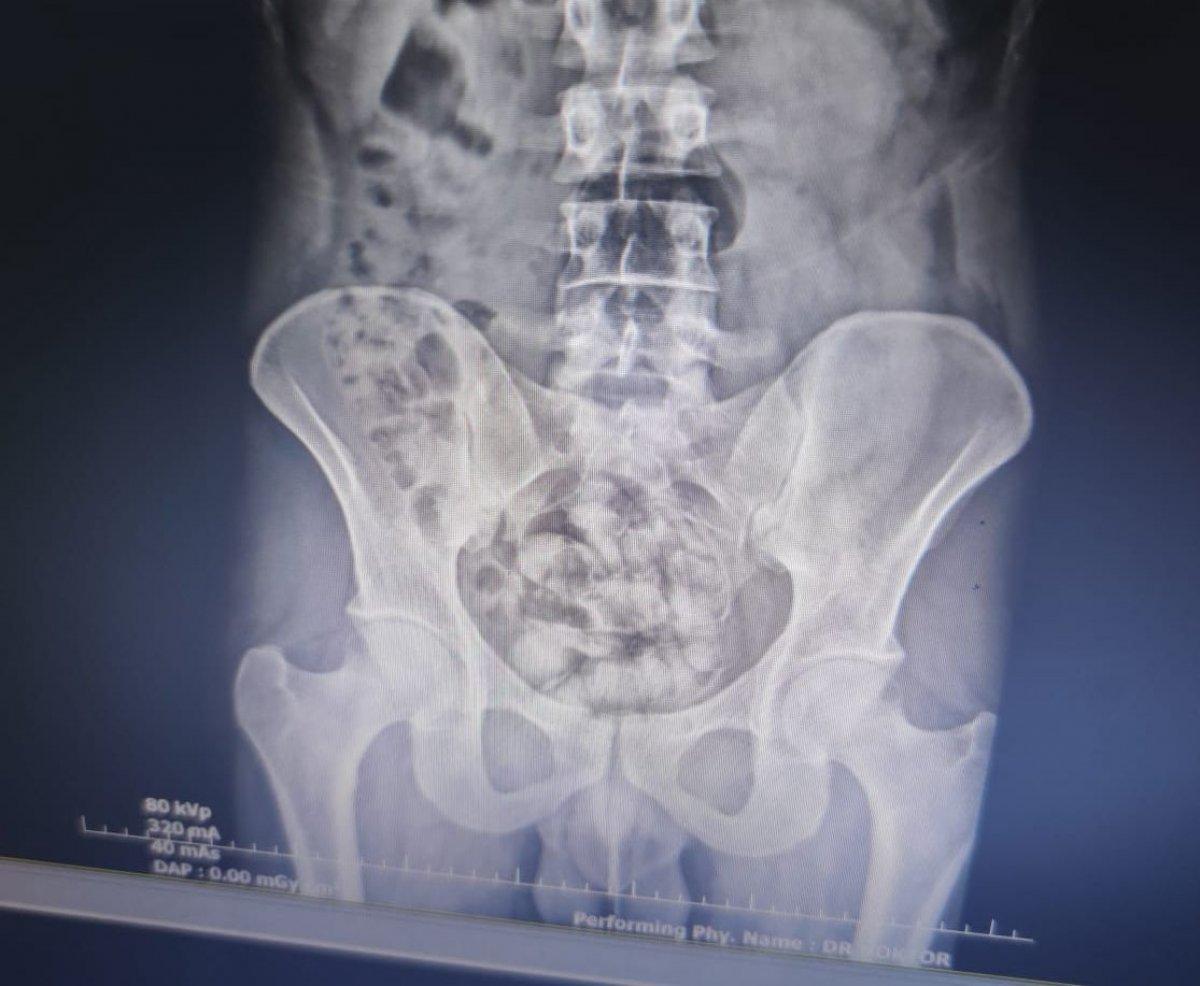

Uyuşturucu baskınlarında İran uyruklu S.Y.'nin röntgen filminde, midesinde 25 kapsül şeklinde uyuşturucu madde olduğu belirlendi.

Burada çekilen röntgen filminde, midesinde 25 kapsül şeklinde paketlenmiş halde 351 gr gelen metamfetamin olduğu tespit edildi.